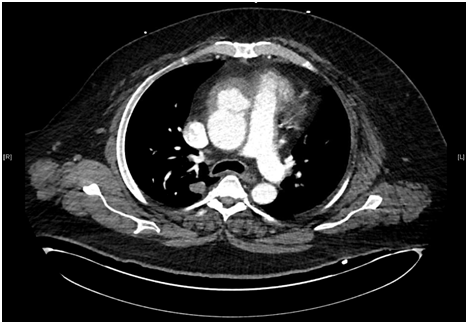

A 57-year-old white male patient with known history of coronary artery disease, morbid obesity, obstructive sleep apnea, hypertension, hyperlipidemia, atrial fibrillation, and tobacco use, presented to a local emergency room with a sudden sharp right arm pain, followed a few hours later by numbness of the right hand. His physical exam was normal except for a very weak pulsation of the right brachial artery. His initial workup included a normal chest x-ray with no acute cardiopulmonary process. A doppler ultrasound of the right upper extremity indicated thrombosis with near-complete occlusion of the distal right brachial artery. He was urgently seen by vascular surgery and underwent thrombectomy of the distal right brachial artery thrombus that was sent for pathology. Hematoxylin Eosin stain and Grocott’s methenamine silver stain showed fungal organisms identified at the thrombus, that had thin septate hyphae with regular branching and that were morphologically consistent with Aspergillus species (Figures 1-6). Subsequently, he was started on intravenous voriconazole, after his EKG, liver function tests were evaluated revealing a normal QTc interval, and liver enzymes respectively. Patient was then evaluated for evidence of disseminated Aspergillosis. His blood cultures have been negative. Aspergillus galactomannan antigen was negative, and his HIV ½ Antibody screen was negative. A computed tomography (CT) scan of the chest with angiography showed an ascending aortic pseudoaneurysm with large soft tissue component, representing a mycotic aneurysm. The contrast opacified lumen of the pseudoaneurysm measured 2.8 x 3.8 cm and there was a portion of the pseudoaneurysm more superiorly that was thrombosed measuring 6.3 x 7.2 cm (Figures 7 & 8). His lungs were clear without evidence of pulmonary nodules or consolidation. CT scan of the brain with contrast and a complete ophthalmological examination were unremarkable. Transthoracic and transesophageal echocardiograms showed no major cardiac finding and no evidence of valvular vegetations. He was then transferred to a tertiary care center where he underwent a homograft of cryopreserved human tissue given the fact that he has an infected mediastinum. He was continued on Voriconazole orally, and he will receive it for life.To note that, five years prior to this event, he underwent an urgent coronary artery bypass grafting (CABG)X3 with reversed autogenous saphenous vein graft from the aorta to the left anterior descending artery, from the aorta to the ramus intermediate, from the aorta to the obtuse marginal artery, along with endoscopic vein harvest left and right greater saphenous veins (from knee to groin bilaterally).

Figure 7 Contrast opacified lumen of the pseudoaneurysm measuring 2.8 x 3.8 cm.